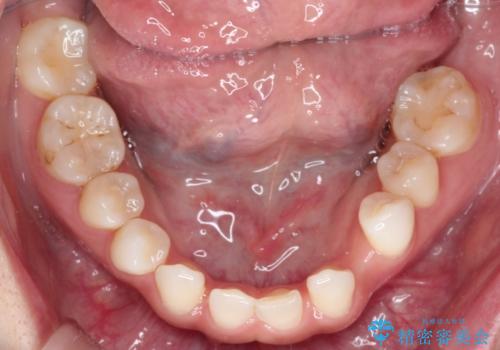

- 空隙歯列を主訴に来院された患者様です。

ばらけている空隙を一箇所に集めながら咬合や正中を改善して最後に補綴治療を行なっています。

右上の臼歯クロスバイトは骨格生のため、そのままにしています。